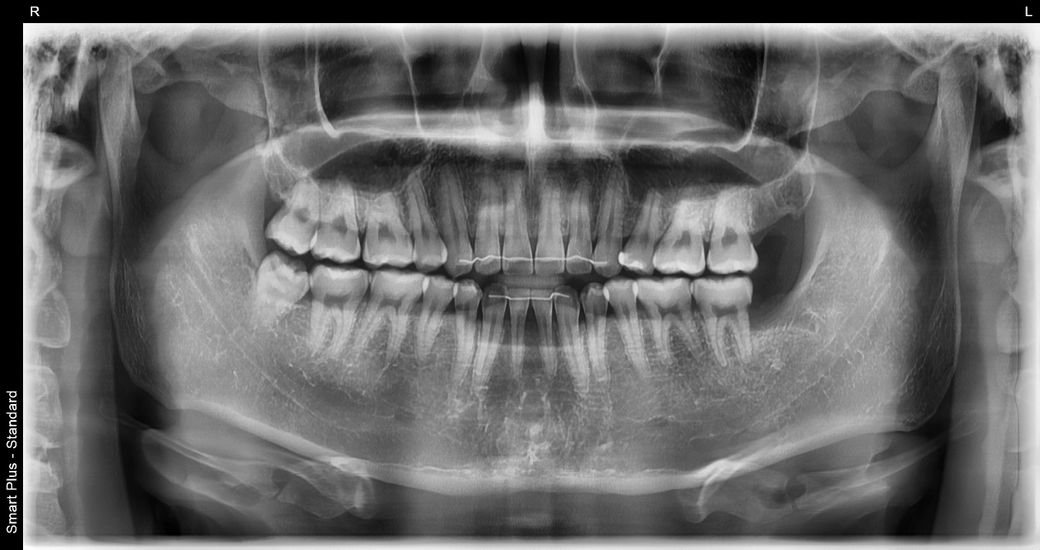

두번째가 깨진 부분들 다 인접면 충치라고 그러던데 다른치과에서 찍은 교익 방사선,파노라마,사진들 모두(각자 다른 치과) 고려했을때 법랑질 뚫고 간 흔적이 안보여서 판독 부탁드리려고 합니다

정말로 인접면 충치인지요..

5/30(휴대폰 겹친 검은음영 참고부탁드립니다..)

싹 다 인레이하자고 하더라고요...

파절된 부위가 보이긴 합니다 하지만 금이 깊게 진행될 정도로 보이는 것은 아닌 것으로 판단이 됩니다 정확한 확인은 직접 확인을 해 봐야 알 수 있습니다.

1. 진단에 있어서 해당 치과에 확신이 안가신다면 다른 치과를 여러군데 다니시고 여러 의견을 듣는것도 도움이 됩니다.

2. 인접면 충치 치료의 경우 진행되기 전 선제적으로 대응하면 좋은 점이 있으나 치과의사마다 판단이 다를 순 있습니다.

3. 사진상으로 추가적으로 확인해봐야할 치아는 #16, #25, #26, #36, #46 입니다